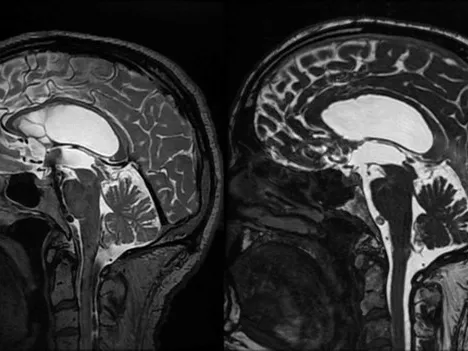

This training is accredited by EACCME with 9 CME credits This fellowship will focus on a practical approach to applying knowledge of neuroanatomy in the radiological interpretation of normal anatomy as well as pathological conditions in the central nervous system.

The course will have three focus areas: anatomy of the brain and its connections, its vascular supply including collaterals and the CSF spaces, which become progressively important in diagnosis intracranial hypo- and hypertension.